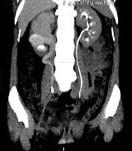

问题 女,44岁,突发性胁腹部绞痛并向会阴部放射伴血尿一次。如图所示,下列说法正确的是 ( )

选项 A、右输尿管结石 B、左肾输尿管未见异常 C、右输尿管中上段扩张 D、右输尿管内可见沿输尿管走行的高密度影 E、右侧肾盂肾盏扩张

答案 ABCDE